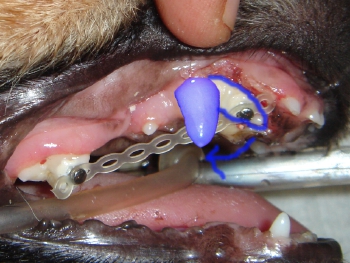

実際移動を予定している犬歯の位置は青い歯で示した場所です。犬歯を矢印で示すように移動させます。

移動中の写真です。

下顎の犬歯が上顎の切歯と犬歯の間に入るようにカバーをします。

前述の写真のコメントです。下顎犬歯カバーにより犬歯を適正な位置に移動させます。